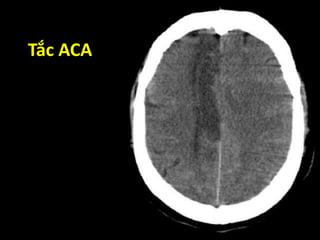

Vùng tưới máu

ACA MCA PCA

Nhìn trên Nhìn dưới

Tắc ACA

Tắc MCA

Tắc PCA